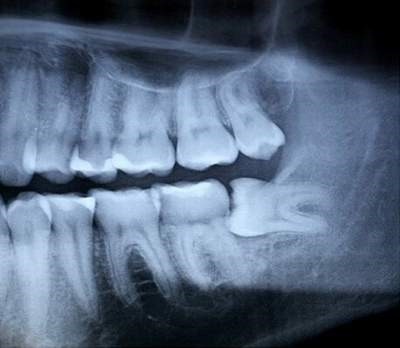

Không phải cứ khi trưởng thành bạn sẽ có răng khôn mà ước tính có khoảng 35% dân số sẽ không mọc răng khôn. Thường thì mỗi người thường có bốn răng khôn ở bốn góc hàm . Vậy câu hỏi đặt ra là với những người này răng khôn nằm ở đâu

Thực chất lúc này răng khôn sẽ “ngoan ngoãn” nằm dưới xương hàm bình yên đến hết đời.